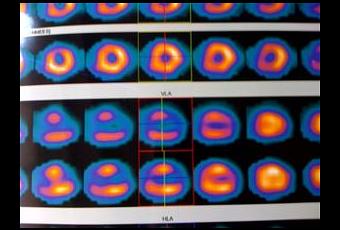

J'ai vu mon cardiologue, qui est content des résultats du test d'effort. On voit très bien la trace laissée par l'infarctus de décembre 2007 (les deux shémas du milieu en bas, l'anneau n'est pas complet), la paroi de la pointe du coeur est devenue à peu près rigide. Aussi, le reste du ventricule s'appuie dessus pour éjecter le sang, ce qui fait que ma fonction ventriculaire gauche globale est normale (FEVG supérieure à 60%). Il n'y a pas de trouble du rythme, et le profil tensionnel est normal.